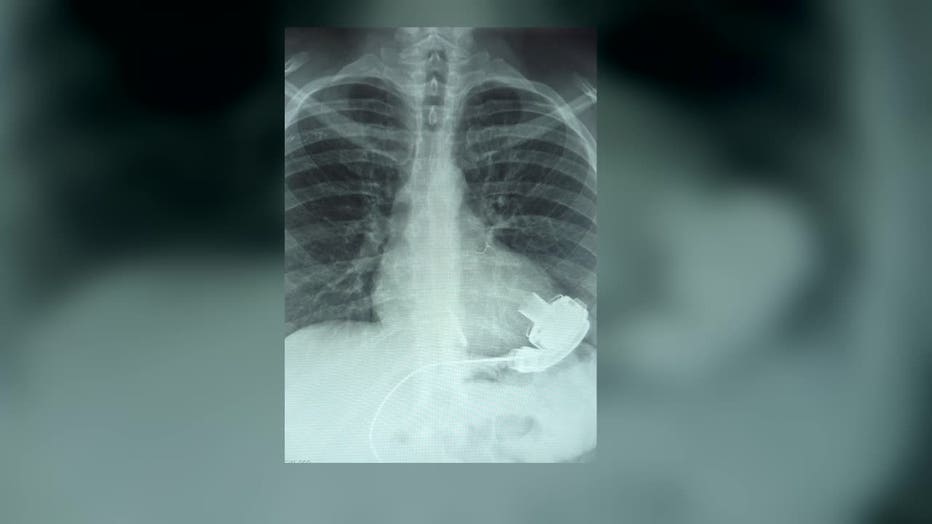

Doctors eventually determined she needed a left ventricular assist device, or LVAD – a mechanical heart implanted in her abdomen to keep her alive until she can receive a transplant.

"There is a turbine in my heart," Kropf explained. "They put a hole on the left apex."